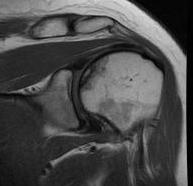

MRI

Sensitivity and specificity approach 100%

T1

- areas low signal intensity on T1 representing edema

- areas of high signal intensity thought to represent blood flow

T2

"Double line sign"

- highly specific for AVN

- inner bright line representing granulation tissue

- outer dark line representing sclerotic bone